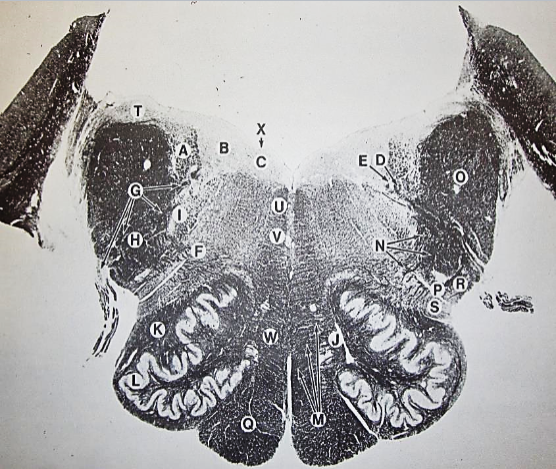

A + B collectively

vestibular nuclear complex

D

solitary fasciculus

E

solitary nucleus

F

nucleus ambiguous

G

fascicles of glossopharyngeal nerve

H

spinal trigeminal tract

I

spinal trigeminal nucleus

J

ventral trigeminothalamic tract

K

central tegmental tract

L

interior olivary nucleus

O

inferior cerebellar peduncle